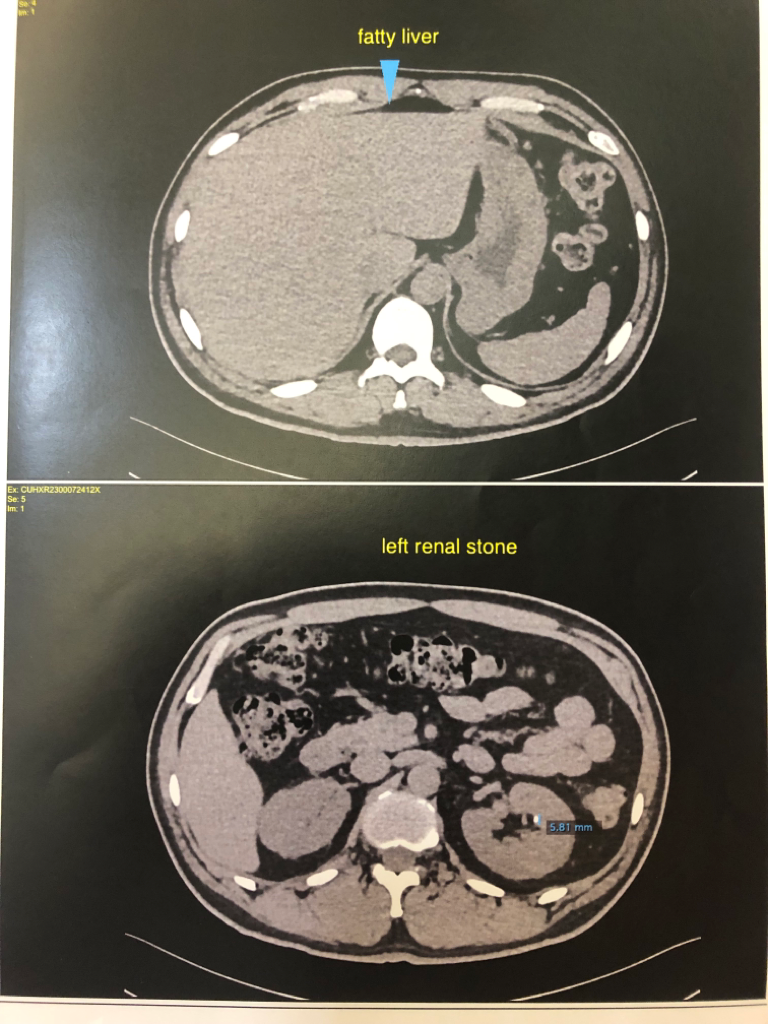

양쪽 부신에 낭종이 있고, 신장에 결석인지 물혹인지가 있고 폐 석회화,경증의 전립선 비대 등등이 있다고 알고 있는데요

• 5번 째 사진

• 6번 째 사진